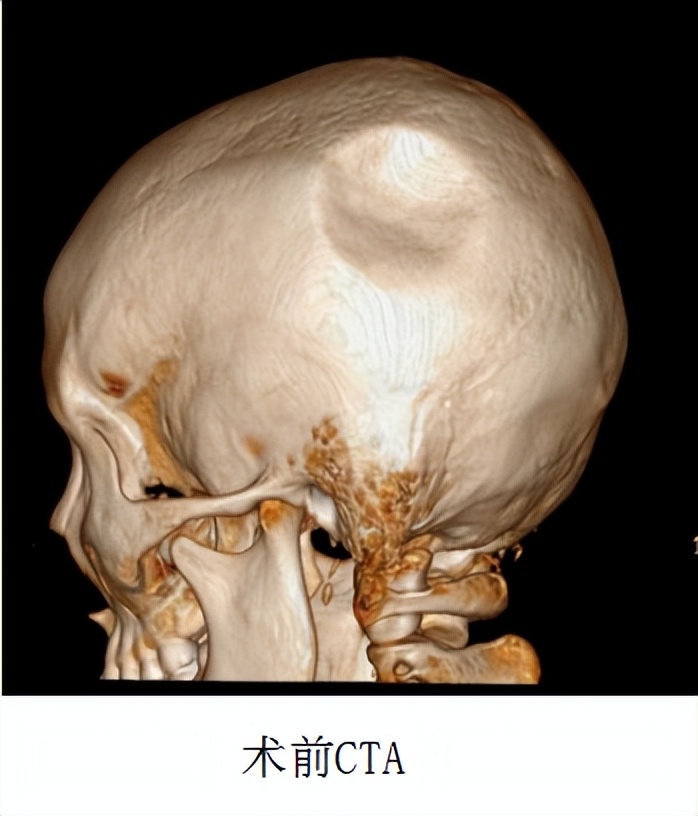

我院神经外七科马赞医师接诊了患者。当时患者的左侧顶枕部出现凹陷性骨折,凹陷范围约为5cm×4cm×1.2cm。

▲术前CT检查所见:左侧顶骨骨质不连,向内凹陷约12mm;左侧顶骨凹陷性骨折,伴左侧顶部硬膜外血肿